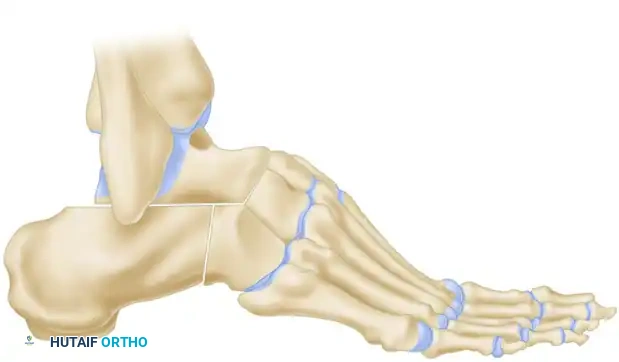

COMPLEX DEFORMITIES: TRIPLE ARTHRODESIS FOR CAVOVARUS AND CALCANEOCAVUS

In cases where the hindfoot varus is rigid, or when severe cavus or calcaneocavus deformities are present (often secondary to poliomyelitis or advanced CMT), soft tissue reconstruction alone will fail. A structural realignment via triple arthrodesis is mandated.

Siffert, Forster, and Nachamie Triple Arthrodesis

For severe cavus deformities, the Siffert, Forster, and Nachamie modification of the triple arthrodesis is highly effective. This technique focuses on resecting a specific dorsal wedge to plantarflex the forefoot and correct the arch.

Biomechanical Goal: A wedge of bone is removed by osteotomy from the midtarsal and subtalar joints. Crucially, the superior part of the talar head is retained to form a structural "beak."

The soft tissue structures anterior to the ankle joint are left undisturbed to maintain vascularity and anterior stability.

In the final position, the forefoot is displaced plantarward, and the dorsal cortex of the navicular is locked securely beneath the remaining "beak" of the talar head. This bony lock prevents dorsal subluxation of the midfoot and maintains the corrected arch height.

Arthrodesis for Calcaneocavus Deformity

Calcaneocavus deformities require a different geometric resection. The primary issue is a vertically oriented calcaneus combined with a plantarflexed forefoot.

A posteriorly based wedge is resected from the subtalar joint.

Following the resection, the entire foot is displaced posteriorly at the subtalar joint. This posterior translation increases the lever arm of the Achilles tendon (if functional) and flattens the longitudinal arch, correcting the calcaneal pitch.